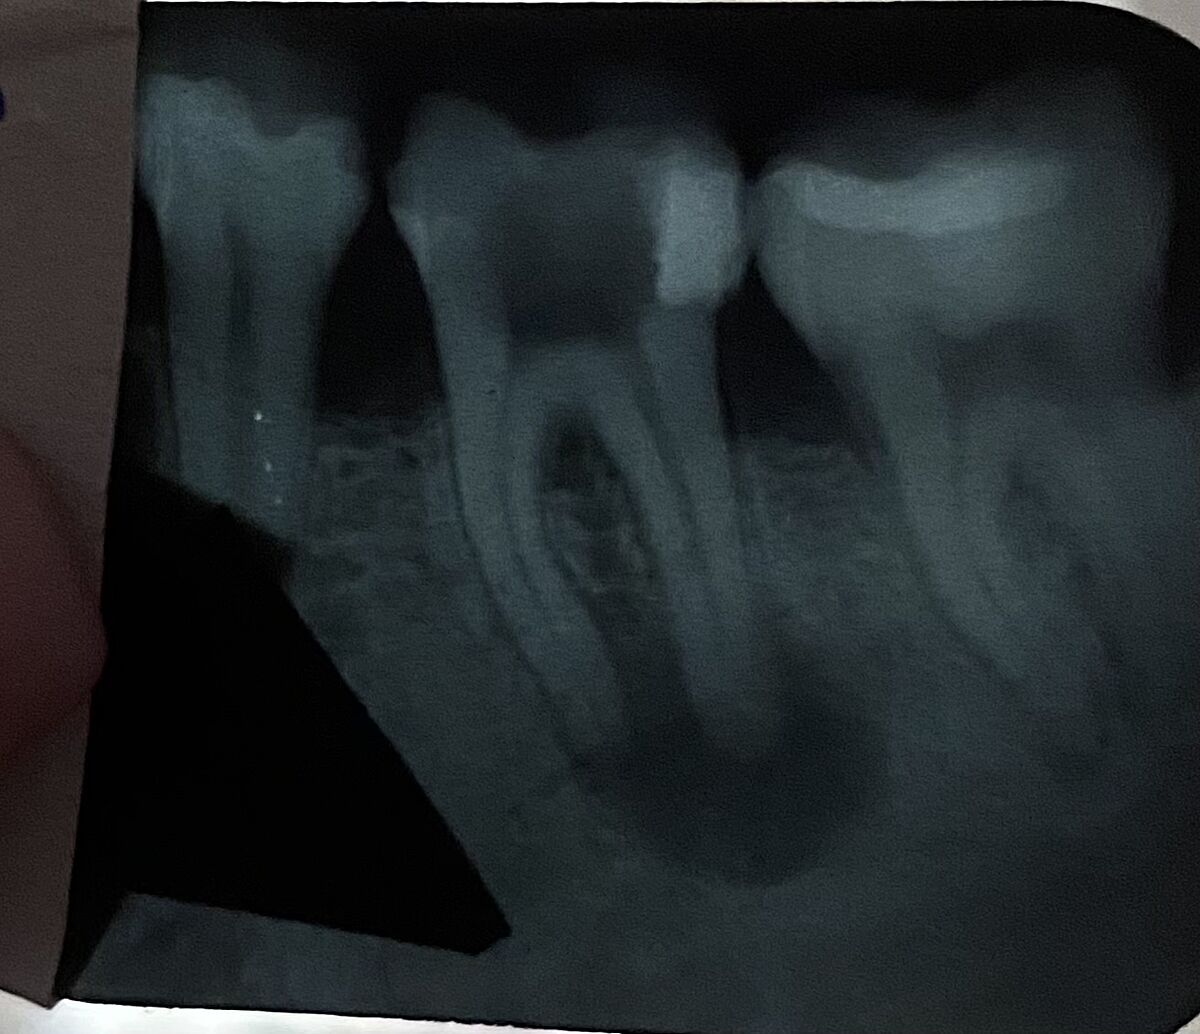

Киста зуба кто удалял

а в идеале еще сделать КТ - там и с соседним нехорошо

Автор выложите здесь свой снимок

Добавила, может кто посмотрит и разбирается

attached-photo

Это снимок из интернета сейчас она добавила свой